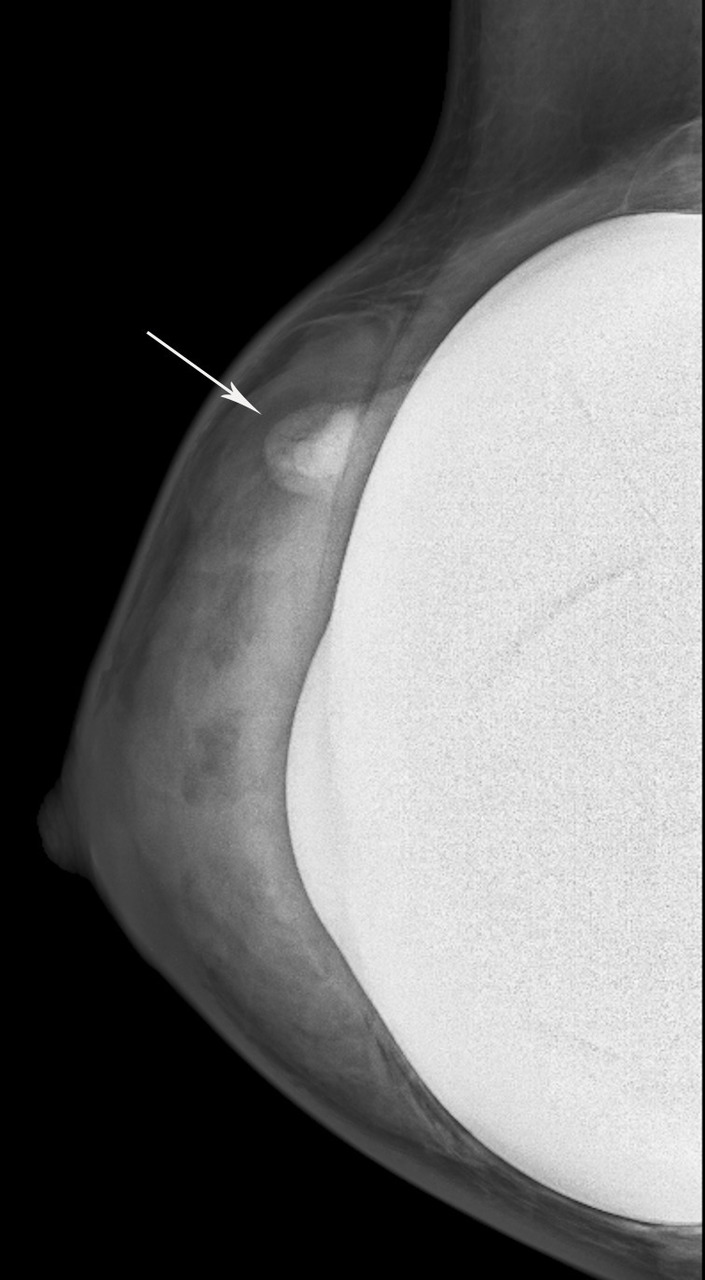

Siliconome : nodule bien régulier, dense en mammographie, hyperéchogène en échographie avec aspect en « tempête de neige » (fig. 5).